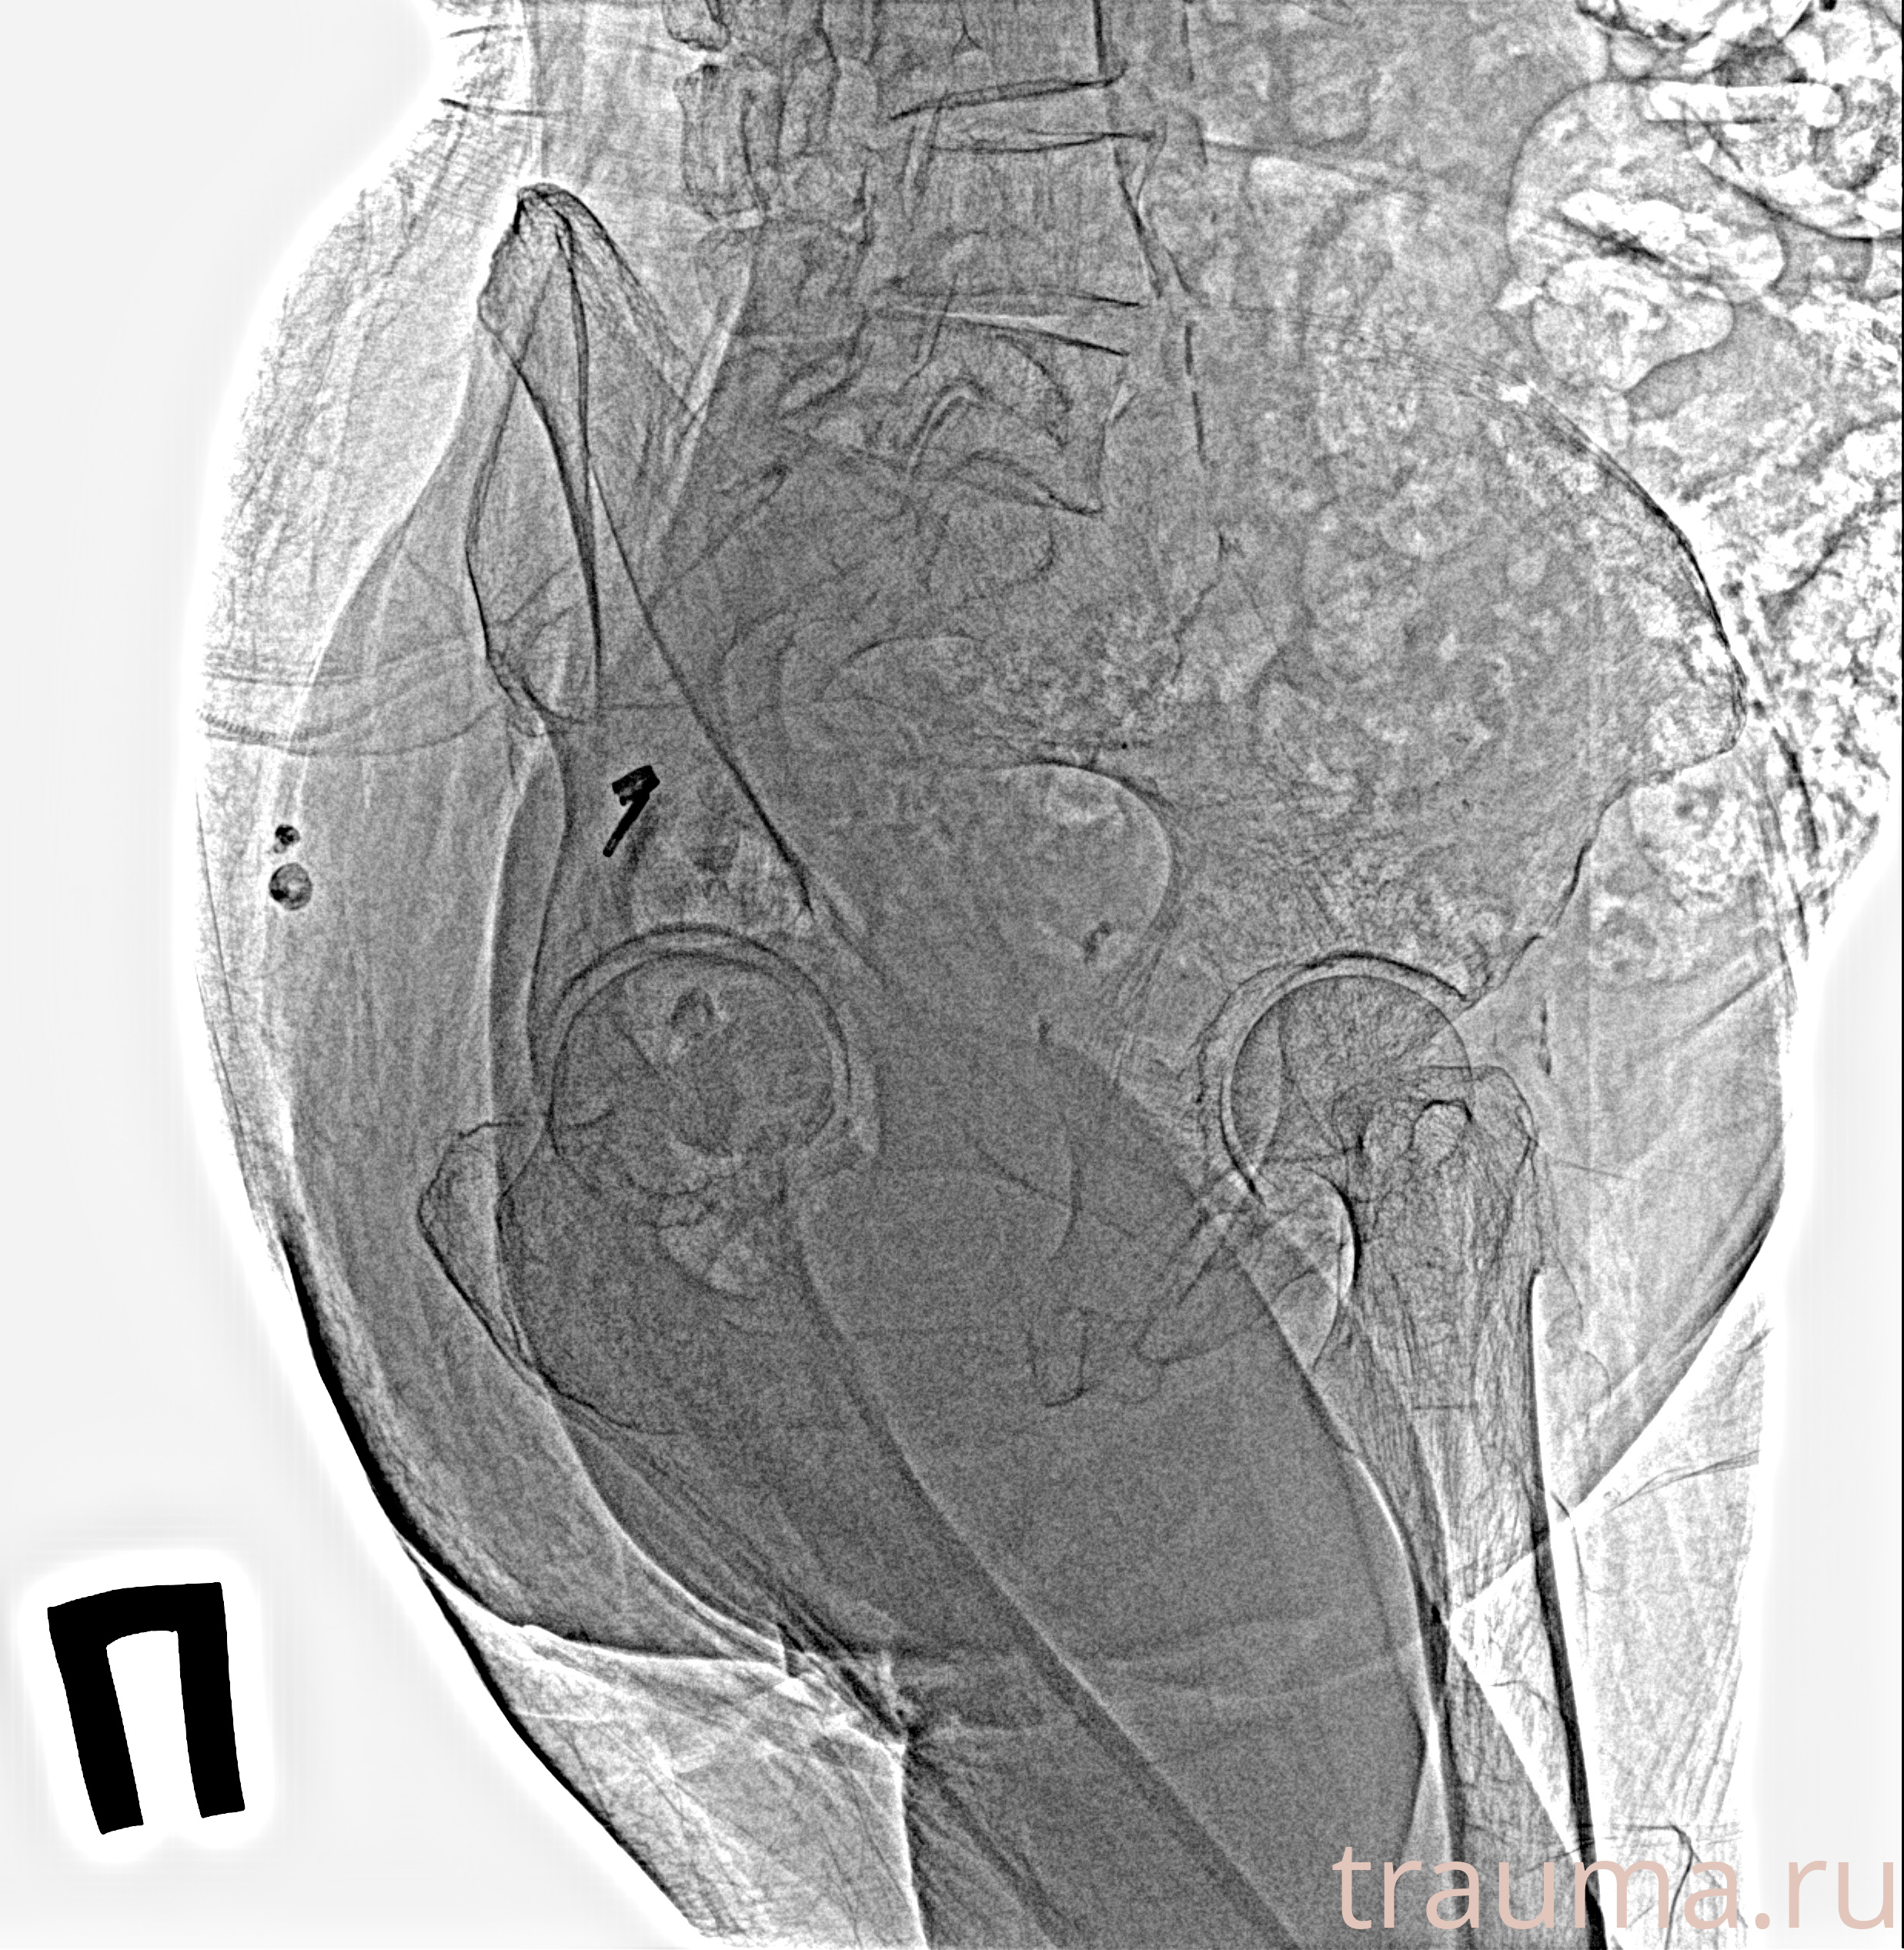

Рентгенограммы

Рентген на дому: по вашему адресу приезжает врач-рентгенолог, травматолог-ортопед с мобильным рентгеновским аппаратом, проводит диагностику травмы или заболевания, делает необходимые рентгенограммы, дает рекомендации по дальнейшему лечению. Получить качественные снимки в домашних условиях возможно благодаря уникальной методике, разработанной МосРентген Центром для института  Склифосовского